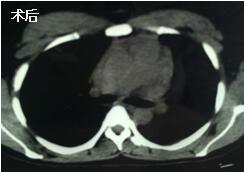

當(dāng)看到病人癥狀緩解,復(fù)查胸部CT幾近完美,我們那種自豪感油然而生。偶爾去治愈,常常去幫助,總是去安慰,我們深知,小伙子的人生之路并不長(zhǎng),只能深深祈禱他在我們的治療下能走得更遠(yuǎn)一些,能把剩下的日子走的更充實(shí)一些。而我們?cè)谀軌驇椭说臅r(shí)候,別一味地去安慰,永不言棄,是我們這一群胸外人堅(jiān)貞的信念。